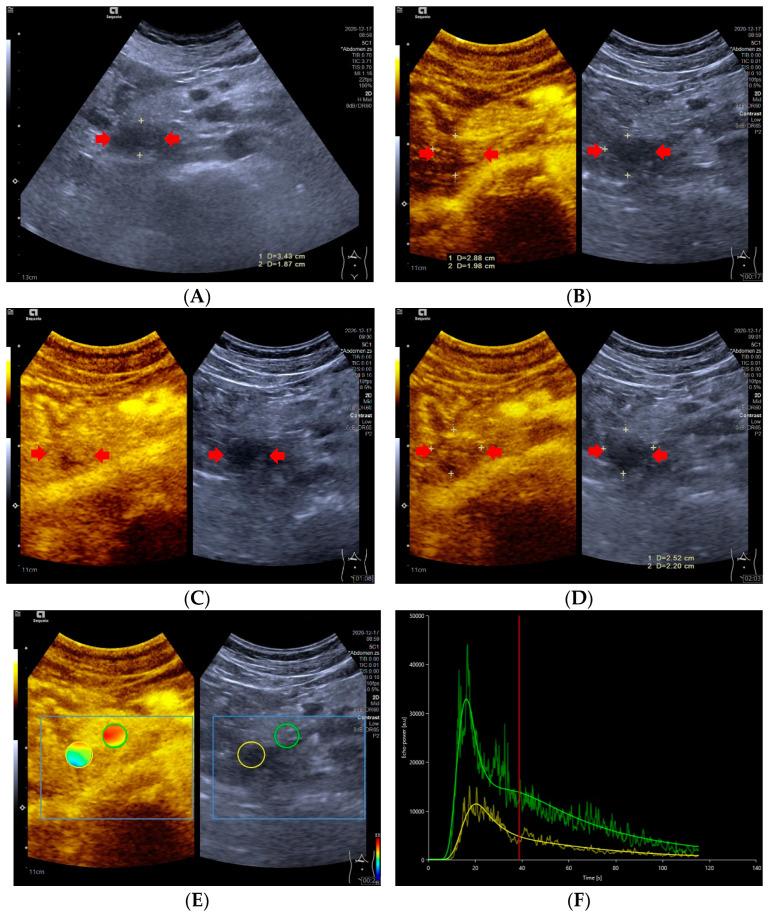

Objective: To investigate whether the dynamic contrast-enhanced ultrasound (DCE-US) analysis and quantitative parameters could be helpful for predicting histopathologic grades of pancreatic neuroendocrine tumors (pNETs). Methods: This retrospective study conducted a comprehensive review of the CEUS database between March 2017 and November 2021 in Zhongshan Hospital, Fudan University. Ultrasound examinations were performed by an ACUSON Sequioa unit equipped with a 3.5 MHz 6C−1 convex array transducer, and an ACUSON OXANA2 unit equipped with a 3.5 MHz 5C−1 convex array transducer. SonoVue® (Bracco Inc., Milan, Italy) was used for all CEUS examinations. Time intensity curves (TICs) and quantitative parameters of DCE-US were created by Vuebox® software (Bracco, Italy). Inclusion criteria were: patients with histopathologically proved pNETs, patients who underwent pancreatic B-mode ultrasounds (BMUS) and CEUS scans one week before surgery or biopsy and had DCE-US imaging documented for more than 2 min, patients with solid or predominantly solid lesions and patients with definite diagnosis of histopathological grades of pNETs. Based on their prognosis, patients were categorized into two groups: pNETs G1/G2 group and pNETs G3/pNECs group. Results: A total of 42 patients who underwent surgery (n = 38) or biopsy (n = 4) and had histopathologically confirmed pNETs were included. According to the WHO 2019 criteria, all pNETs were classified into grade 1 (G1, n = 10), grade 2 (G2, n = 21), or grade 3 (G3)/pancreatic neuroendocrine carcinomas (pNECs) (n = 11), based on the Ki−67 proliferation index and the mitotic activity. The majority of the TICs (27/31) of pNETs G1/G2 were above or equal to those of pancreatic parenchyma in the arterial phase, but most (7/11) pNETs G3/pNECs had TICs below those of pancreatic parenchyma from arterial phase to late phase (p < 0.05). Among all the CEUS quantitative parameters of DCE-US, values of relative rise time (rPE), relative mean transit time (rmTT) and relative area under the curve (rAUC) were significantly higher in pNETs G1/G2 group than those in pNETs G3/pNECs group (p < 0.05). Taking an rPE below 1.09 as the optimal cut-off value, the sensitivity, specificity and accuracy for prediction of pNETs G3/pNECs from G1/G2 were 90.91% [58.70% to 99.80%], 67.64% [48.61% to 83.32%] and 85.78% [74.14% to 97.42%], respectively. Taking rAUC below 0.855 as the optimal cut-off value, the sensitivity, specificity and accuracy for prediction of pNETs G3/pNECs from G1/G2 were 90.91% [66.26% to 99.53%], 83.87% [67.37% to 92.91%] and 94.72% [88.30% to 100.00%], respectively. Conclusions: Dynamic contrast-enhanced ultrasound analysis might be helpful for predicting the pathological grades of pNETs. Among all quantitative parameters, rPE, rmTT and rAUC are potentially useful parameters for predicting G3/pNECs with aggressive behavior.

目的